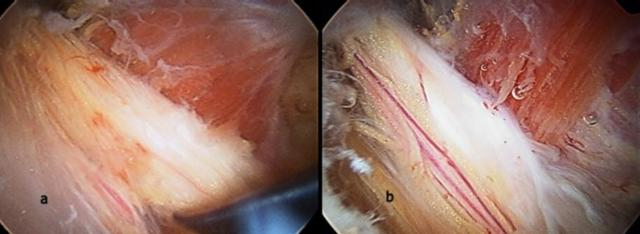

左图:正常的梨状肌和坐骨神经解剖(P:梨状肌 SN:坐骨神经)

右图:梨状肌损伤后在坐骨神经表面形成粘连的纤维束带

a:梨状肌综合征患者因纤维束带卡压导致坐骨神经水肿变平

b:关节镜下微创神经松解术后神经表面血管恢复正常